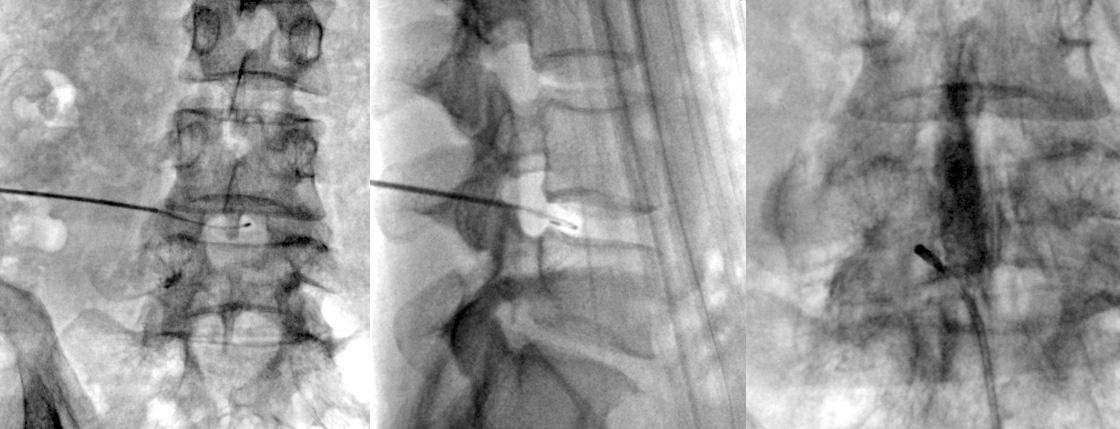

직경 2mm 이내의 가느다란 주사바늘을 문제가 생긴 디스크에 병변에 고주파에너지를 쏘아 척추신경을 압박하는

디스크내의 분자를 분해하고 녹인 후 수축 응고시키는 치료 방법입니다.

전신마취가 아닌 부분 마취 후 간단한 시술방법으로 조기 보행이 가능하고, 심하게 무너진 척추골의 높이를 교정할 수 있습니다.